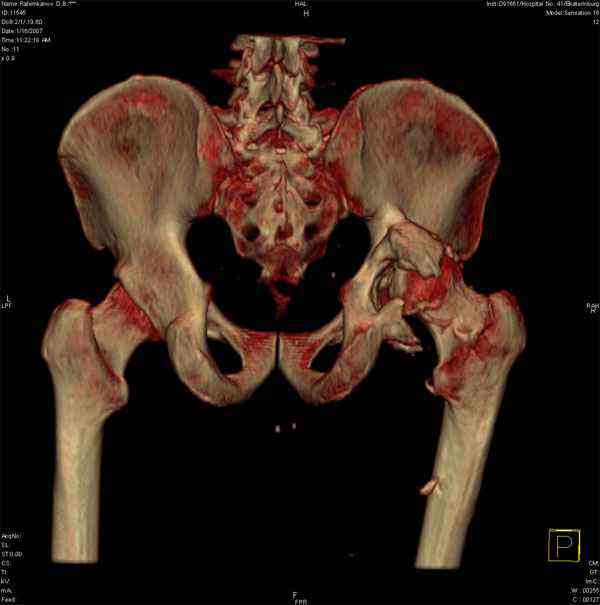

Еще одно наблюдение, неправильно сросшийся перелом заднего отдела ВВ с ввихом головки бедра 16-и летней давности.

С уважением, Р.Тихилов

Большое спасибо за ответ, примеры впечатляют, особенно случай с переломом задней колонны. Интересно отличаются ли у Вас доступ при значительных проблемах в задних отделах от стандартного, всегда ли хватает головки или берете кость из других мест, отличается ли послеоперационное ведение у таких больных (когда нагрузка?).